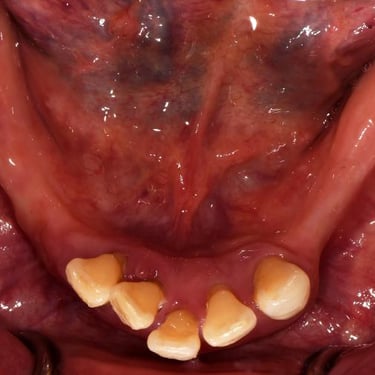

Edentulismo completo

El edentulismo completo es la ausencia total de dientes en una o ambas arcadas.

Los pacientes tienen dificultad para masticar, hablar y pueden sentirse incómodos con su apariencia.

El tratamiento puede incluir la colocación de una prótesis completa sobre implantes, proporcionando una solución fija y estable